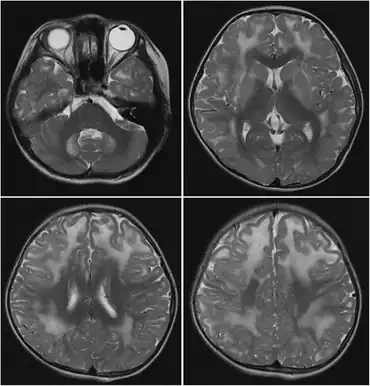

The L-2 form is more common, severe, and mainly affects the central nervous system. The basal ganglia are affected, and cystic cavitations in the white matter of the brain are common, beginning in infancy. This form is chronic, with early symptoms such as hypotonia, tremors, and epilepsy declining into spongiform leukoencephalopathy, muscular choreodystonia, mental retardation, and psychomotor regression.[4]